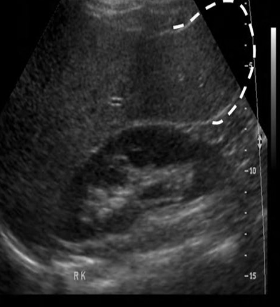

Identify this image.

Cirrhosis